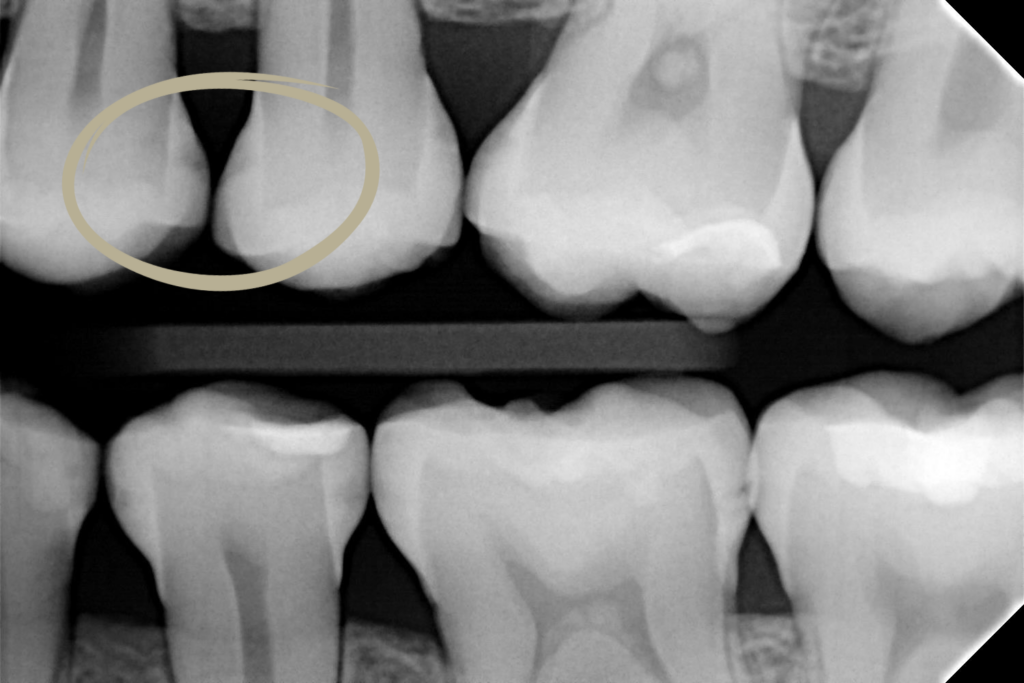

Icon Proximal – leczenie zmian próchnicowych na powierzchniach stycznych

• Wczesne zmiany próchnicowe (do granicy zewnętrznej 1/3 zębiny), wykrywane na zdjęciu skrzydłowo-zgryzowym.

• Brak ubytków wymagających mechanicznego opracowania.

• Alternatywa dla tradycyjnego leczenia wiertłem w przypadku początkowej próchnicy.